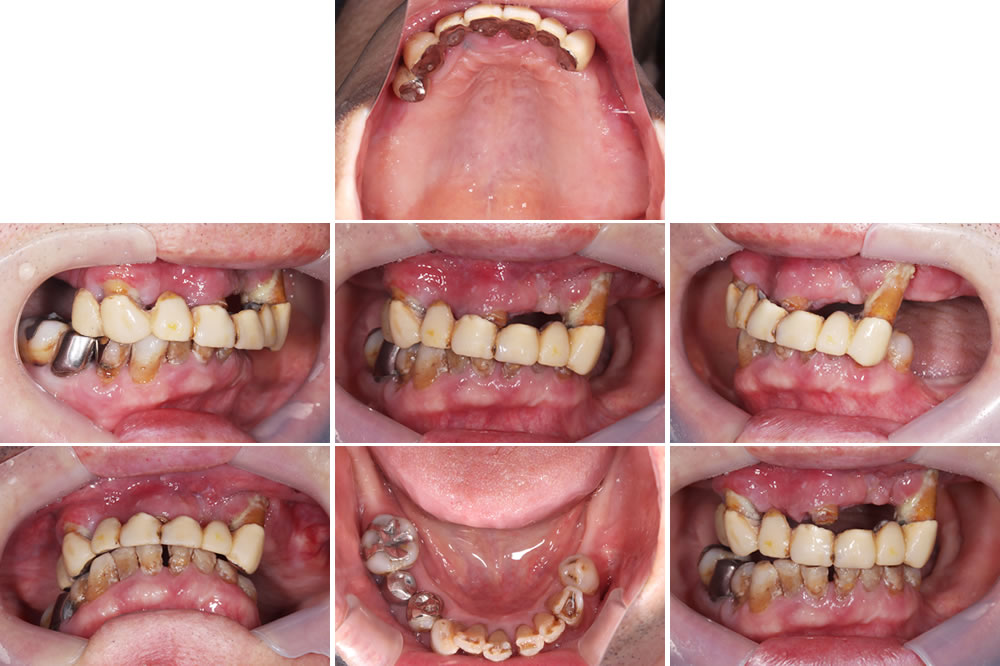

こちらの患者さまは、上の歯が抜けそうとの主訴で来院されました。上顎ブリッジが大きく動揺している状態、下の歯は動揺はありませんでしたが、全体的に虫歯や歯石の沈着が確認できました。

レントゲン検査

レントゲン精査を実施。上顎残存歯は歯を支える骨がほとんどなくなっており、保存するのは不可能な状態(重度歯周炎)と診断しました。